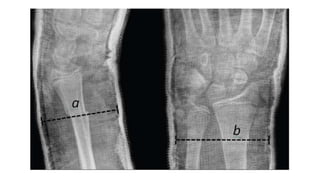

 Cast Index (CI), defined as ratio of inner

diameter of the cast in lateral view to that in

AP view was measured at the fracture site in all

the radiographs.

 The CI is a simple reliable radiographic

measurement to predict and analyze the

redisplacement of distal forearm fractures in

children

 This original paper describing the

recommended a CI of <0.7